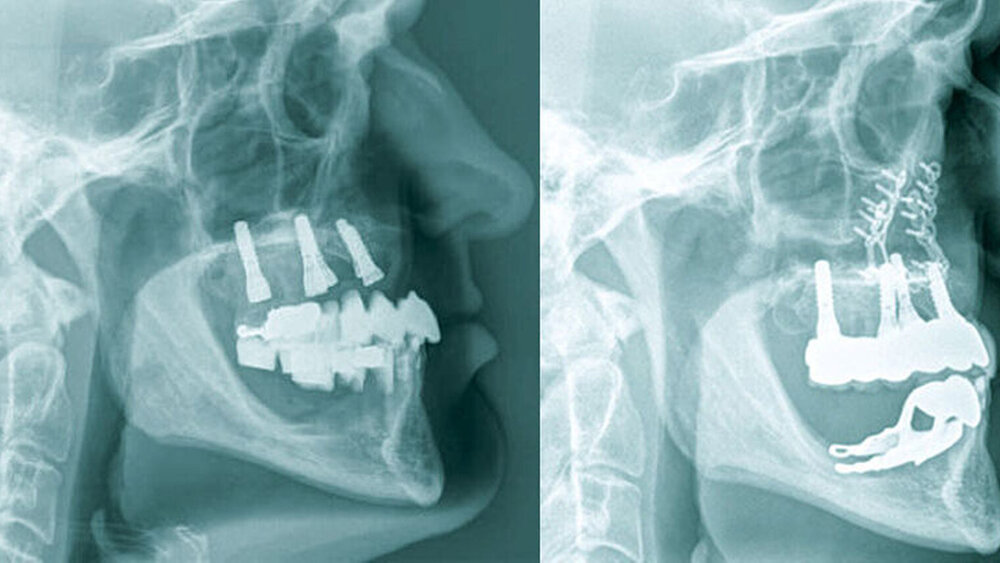

Die klinische Situation zeigte einen atrophierten, teilbezahnten Oberkiefer (herausnehmbarer, nicht implantatgetragener Zahnersatz) sowie einen teilbezahnten Unterkiefer (herausnehmbarer, mit Klammern verankerter Interimszahnersatz) (Abbildung 1). Vor allem fiel der prothetisch eingestellte Kopfbiss im Frontzahnbereich mit ausgeprägter negativer sagittaler Stufe bei einer Rücklage des Oberkiefers von 0,8 cm auf. In der alio loco angefertigten prä-implantologischen Röntgendiagnostik mittels Panoramaschichtaufnahme war dies nicht zu erkennen. Aufgrund des klinischen Bildes eines defizitären Mittelgesichtsprofils erfolgte eine kephalometrische Analyse. Hier bestätigten die ermittelten Werte eine maxilläre Retrognathie (Angle-Klasse III; Abbildung 2).

Insgesamt lag somit eine prothetisch schwierig zu versorgende Situation vor, weshalb nach ausführlicher interdisziplinärer Besprechung gemeinsam mit dem Patienten die Entscheidung zugunsten einer Le-Fort-I-Osteotomie zur Behebung der sklelettalen Fehlstellung und zur Verbesserung des Gesichtsprofils getroffen wurde. Simultan konnten die in situ befindlichen Implantate für den provisorischen Zahnersatz im Sinne eines Operationssplints genutzt werden. Nach der Modelloperation am Artikulator und der Anfertigung sowie der Eingliederung eines individuellen CAD/CAM-gefrästen temporären Zahnersatzes (Poly-Temp®, ceramill®; Amann Girrbach GmbH, Pforzheim, Deutschland) im Oberkiefer (Abbildung 3) erfolgte die maxilläre Umstellungsosteotomie mittels Osteotomie in Le-Fort-I-Ebene. Die temporäre Restauration sicherte intra- und postoperativ die Kieferrelation und Okklusion (Abbildung 4).